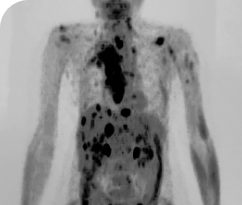

BASELINE

AFTER 31 MONTHS

33-YEAR-OLD MALE4

PATIENT CASE:

METASTATIC, RAIa-REFRACTORY,

PAPILLARY THYROID CANCER1,2

- 33-year-old male

- Progression on RAI and first line systemic therapy

- PRa after 2 cycles of VITRAKVI® (larotrectinib)

- Confirmed partial response on VITRAKVI lasting 55 cycles

Clinical presentation1

- Initially diagnosed at age 27

- Bulky disease in neck and thoracic involvement; metastatic, RAI-refractory papillary thyroid cancer

Prior treatments and outcomes1

- 5 prior surgeries

- 2 prior RAI treatments

- Systemic therapy with pazopanib and trametinib

Testing1,2

- ETV6a-NTRK3a gene fusion was detected during disease progression on systemic therapy via NGS

VITRAKVI treatment1

- VITRAKVI 100 mg twice daily orally

Response to VITRAKVI1,2

- Confirmed partial response (92.6% reduction in target lesions)

- Treatment continued for 55 cycles

- VITRAKVI was well tolerated; patient did not have to discontinue due to AEa

- No treatment interruptions or dose reductions

Response in primary and metastatic lesions1